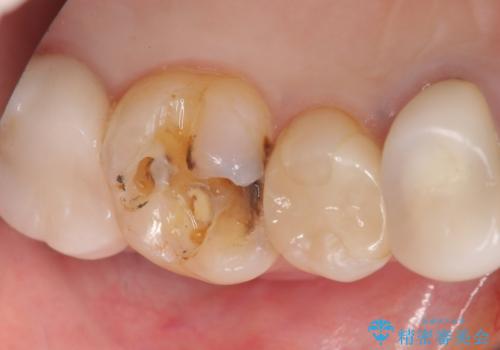

精査したところ、奥歯のメタルインレー(銀の詰め物)の下でう蝕が広がっていました。

う蝕を丁寧に除去したのち、セラミックインレーによる補綴治療を行いました。